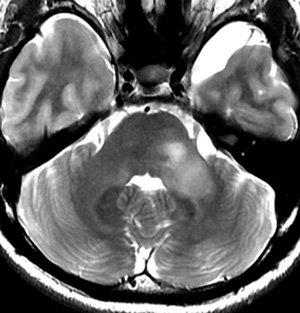

NF-1 20代成人のpontine glioma

少しmass effectもあり,診断名としてはdiffuse pontine gliomaというしかないのですが,何もしないで放置します。それでも大きくなったりしません。